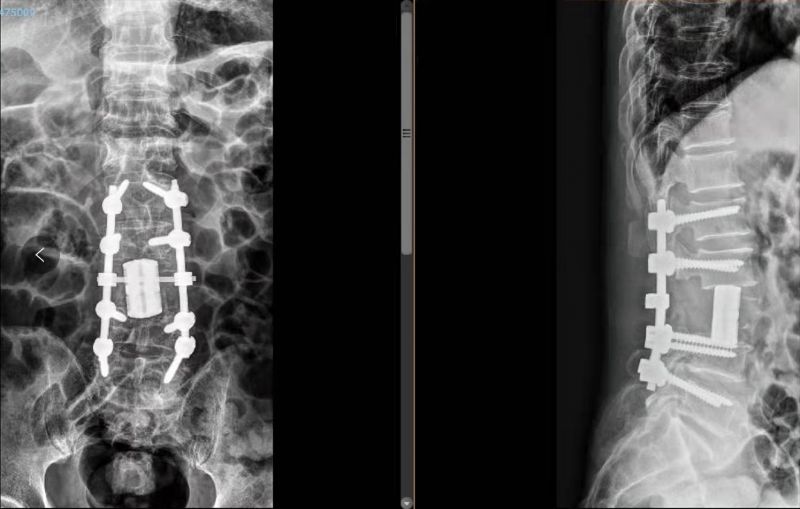

3D打印术后人工椎体植入脊柱重建良好。